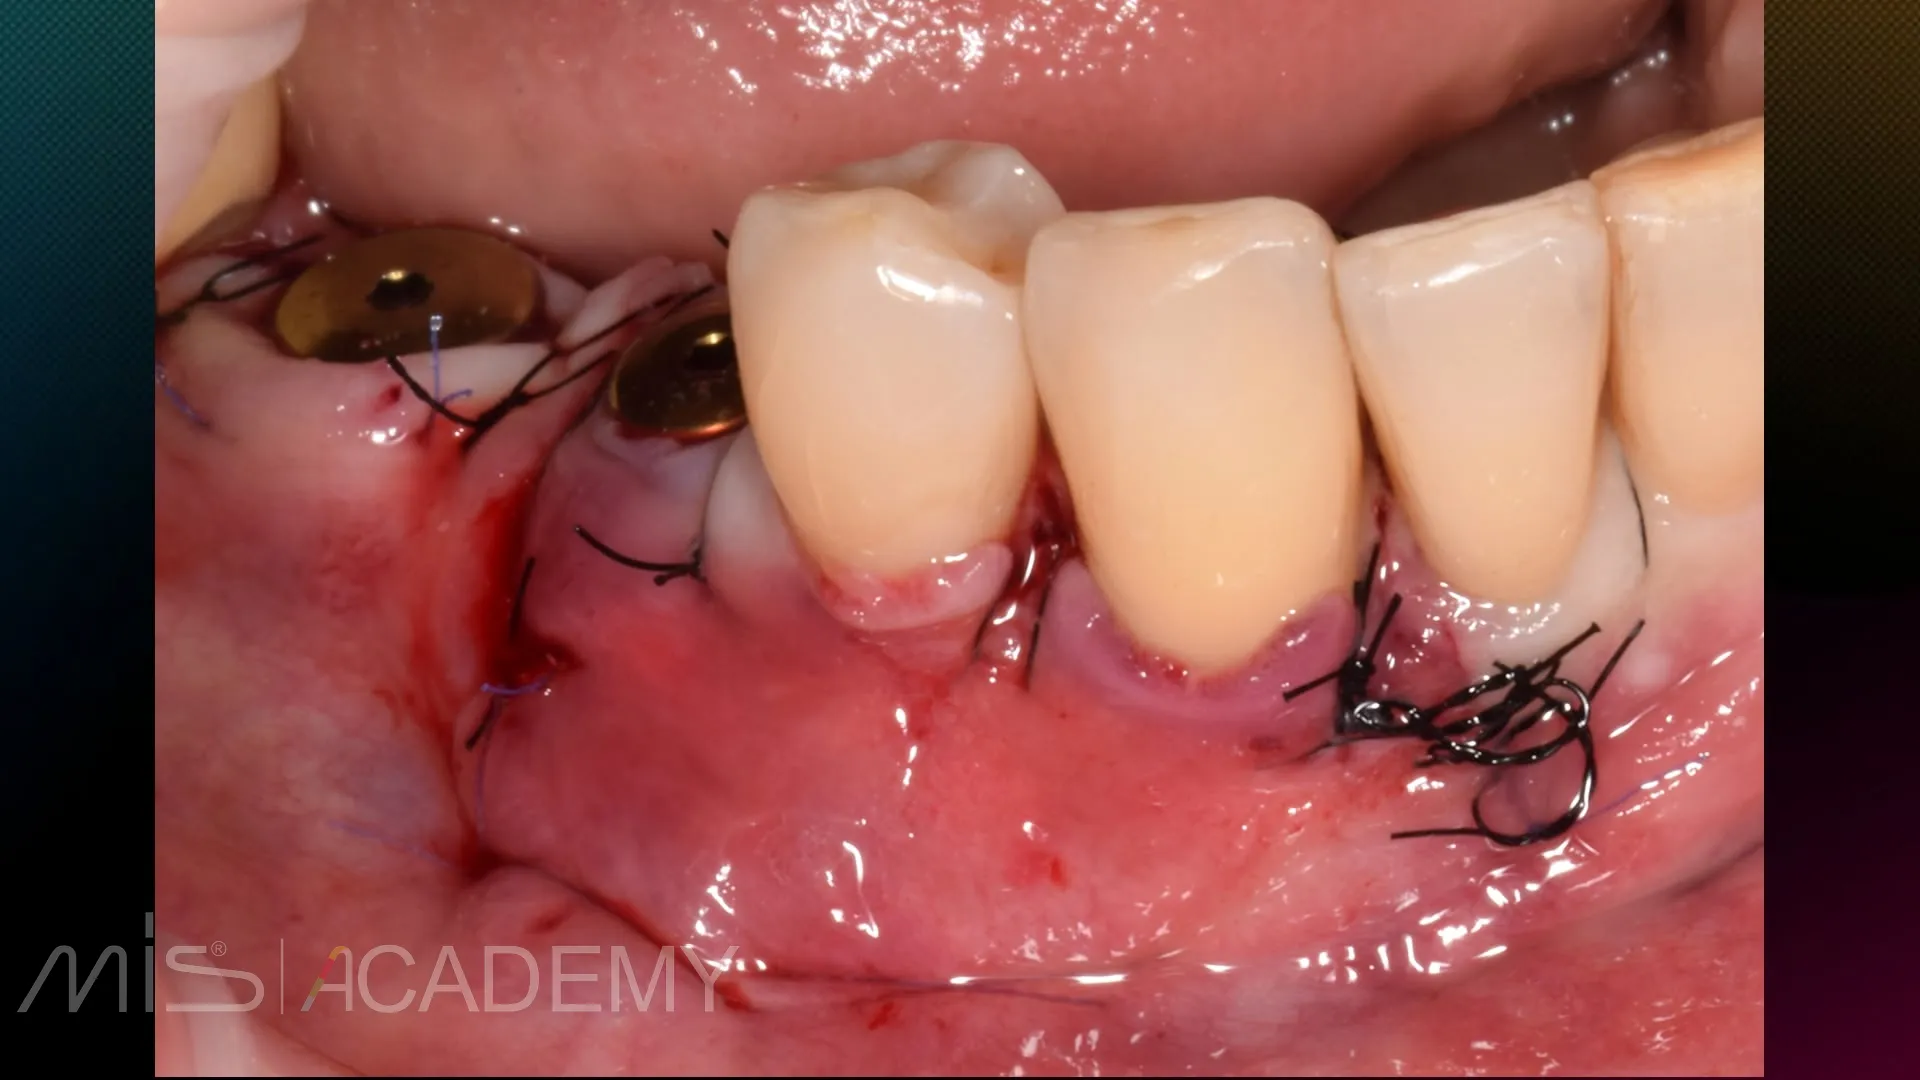

— Работа с мягкими тканями вокруг имплантатов.

— Хирургическое закрытие рецессий на зубах 4.3, 4.4 методикой КСЛ.